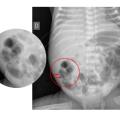

Entérocolite ulcéronécrosante

L’entérocolite ulcéronécrosante (ECUN) est une complication digestive redoutée en néonatologie, par sa capacité à mettre en jeu le pronostic vital brutalement et par la morbidité séquellaire qu’elle peut entraîner. En France, elle touche environ 5  % des enfants nés avant 32 semaines d’aménorrhée  ; elle est d’autant…